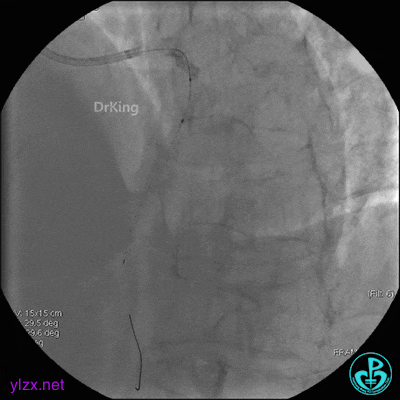

4 急诊冠脉造影

左主干轻度狭窄,左主干到前降支近端钙化影明显。前降支开口严重狭窄,近端闭塞。粗大回旋支轻度狭窄。

右冠脉无严重狭窄,右冠脉没有给前降支提供逆向供血。